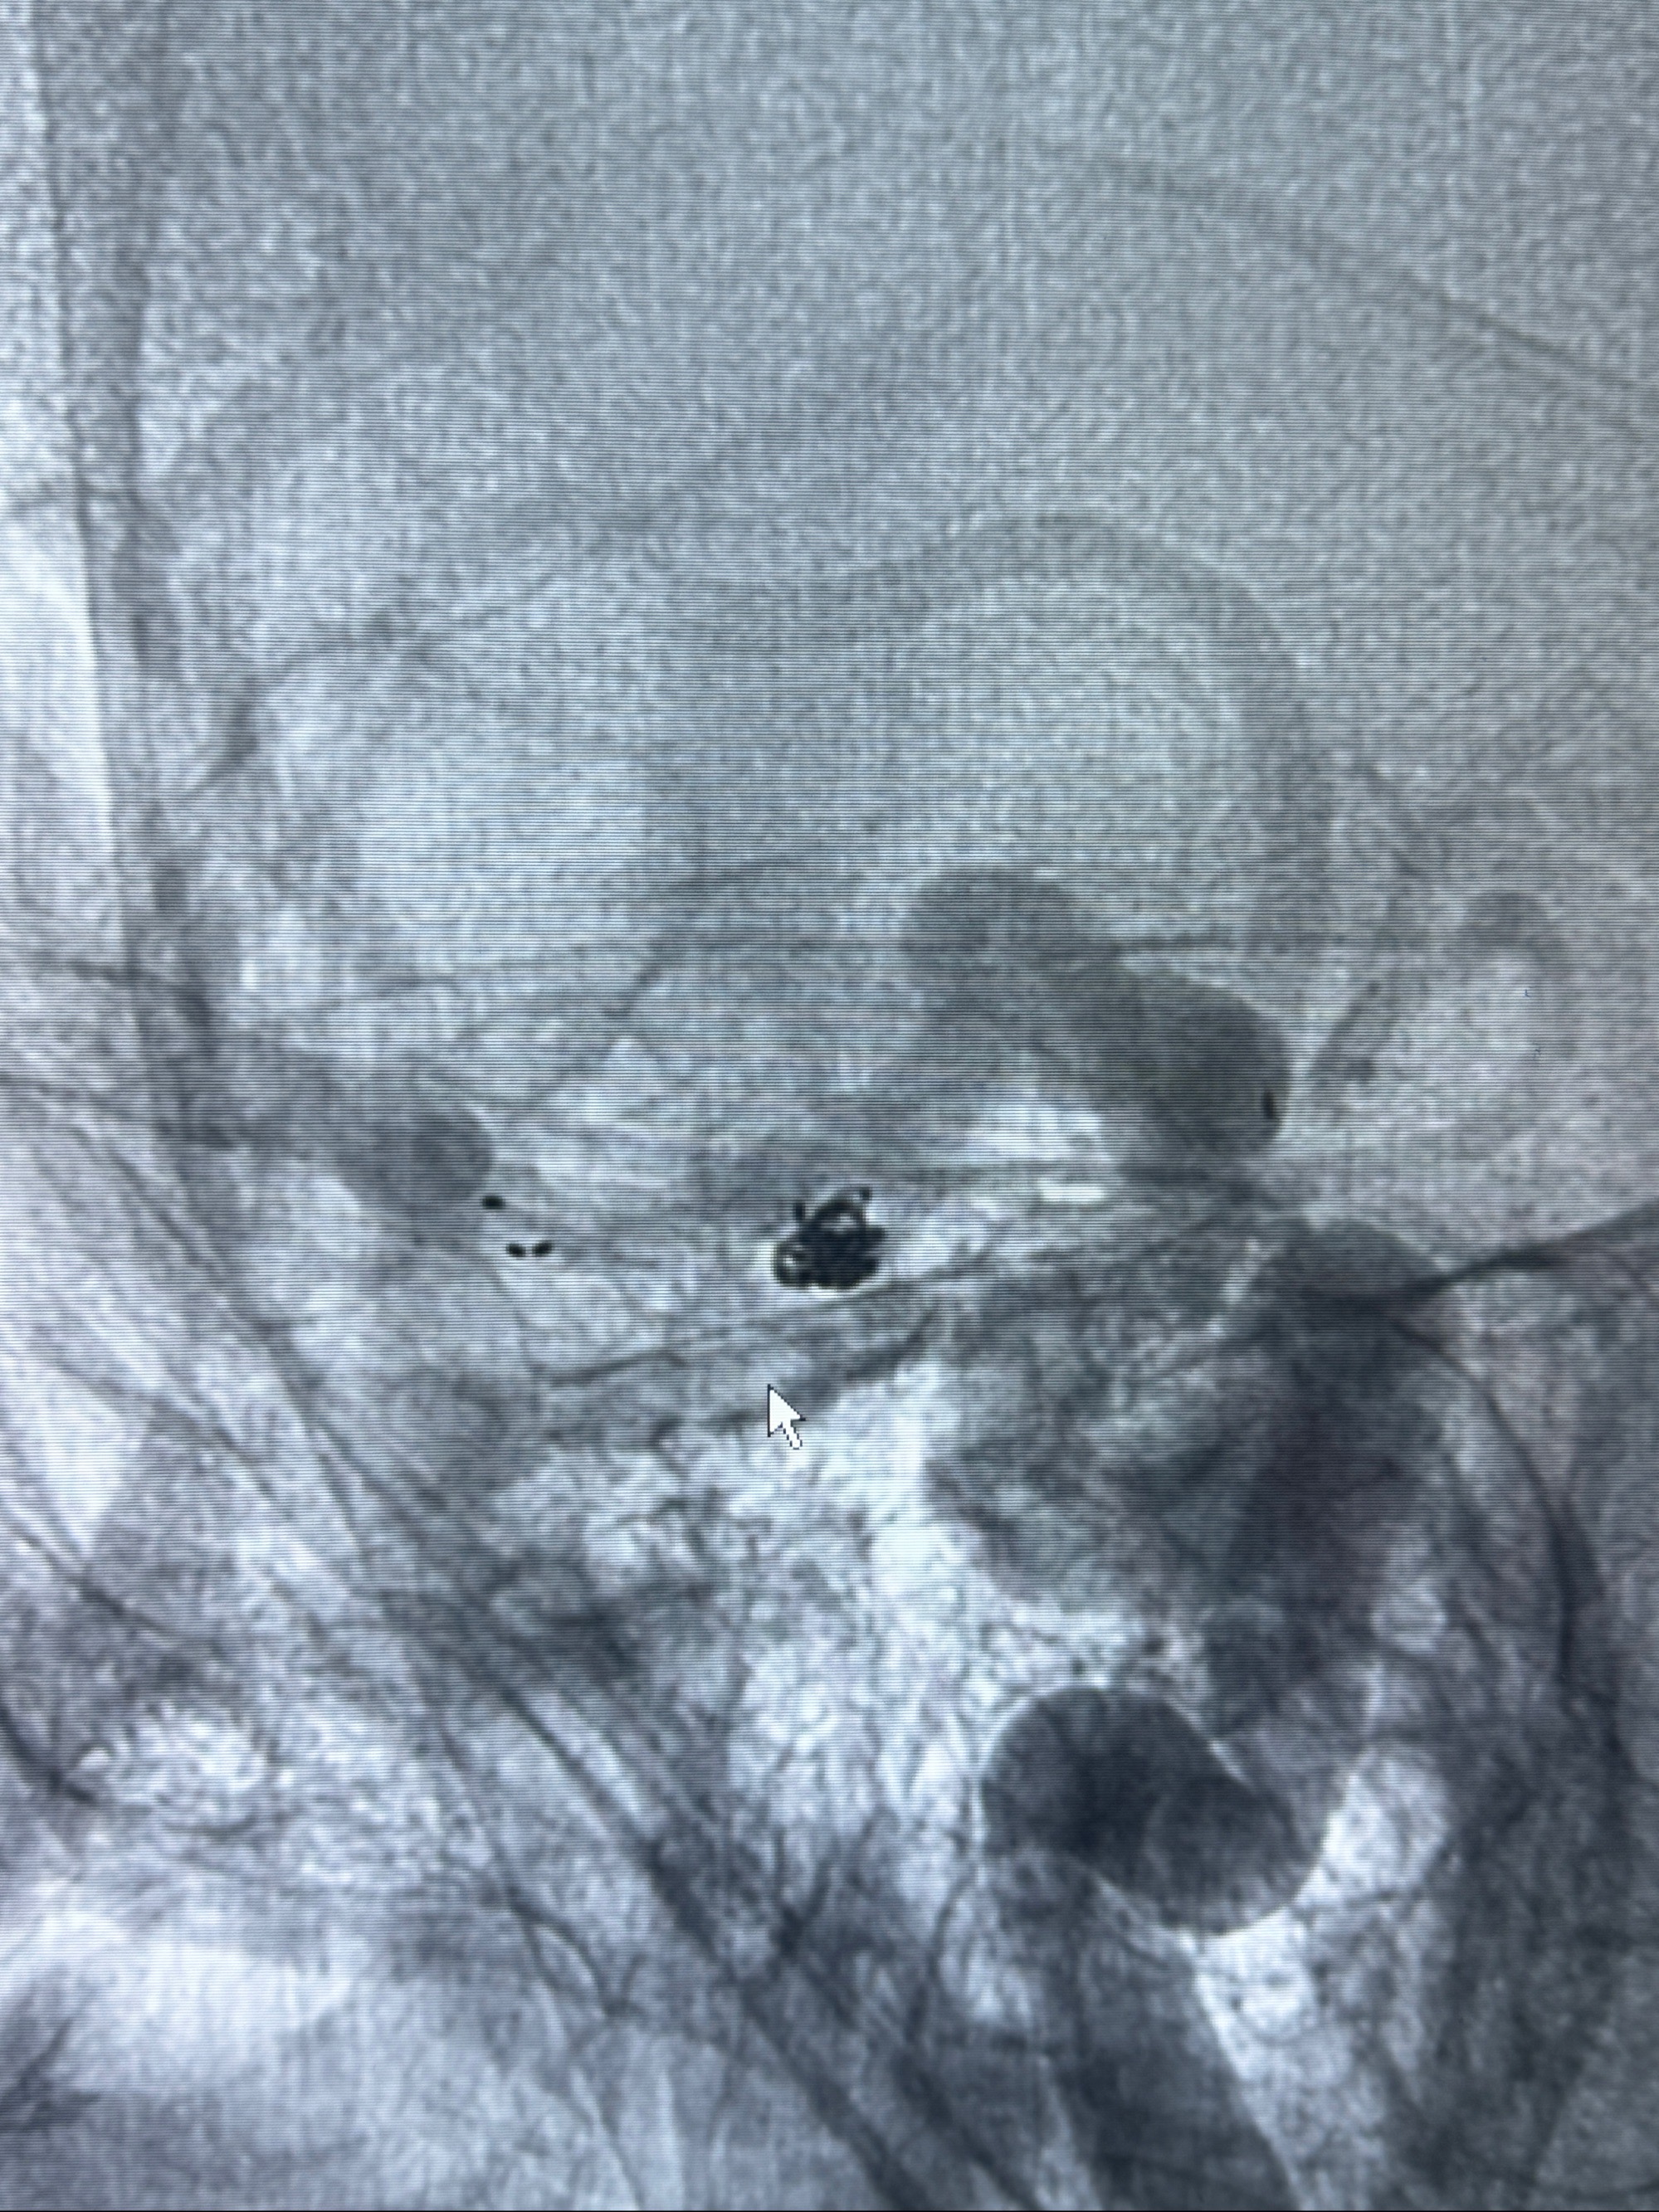

2023-12-04全麻下行支架辅助治疗

S-AB4-20mm

麻醉苏醒佳,遵嘱动作

术后即刻CT